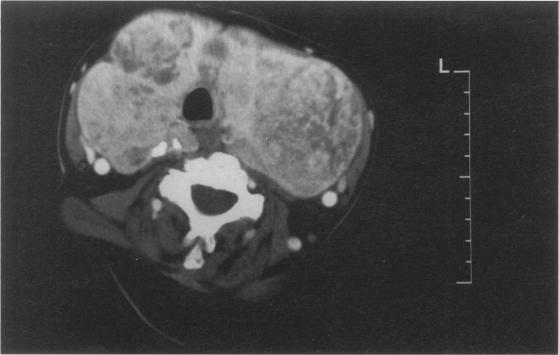

Use of the laryngeal mask airway combined with fibre-optic laryngoscopy in thyroid surgery was first described in 1991. In this unit, it has been successfully used in over 130 cases. The advantages in identification and preservation of the recurrent laryngeal nerves using this technique have been demonstrated. However, to date, no report exists of a further advantage, namely the management of tracheomalacia.

1991年首次报道了在甲状腺手术中使用喉罩气道联合纤维喉镜。在本科室,该方法已成功应用于130余例病例。已证实使用该技术在识别和保护喉返神经方面具有优势。然而,迄今为止,尚无关于另一优势即气管软化处理的报道。